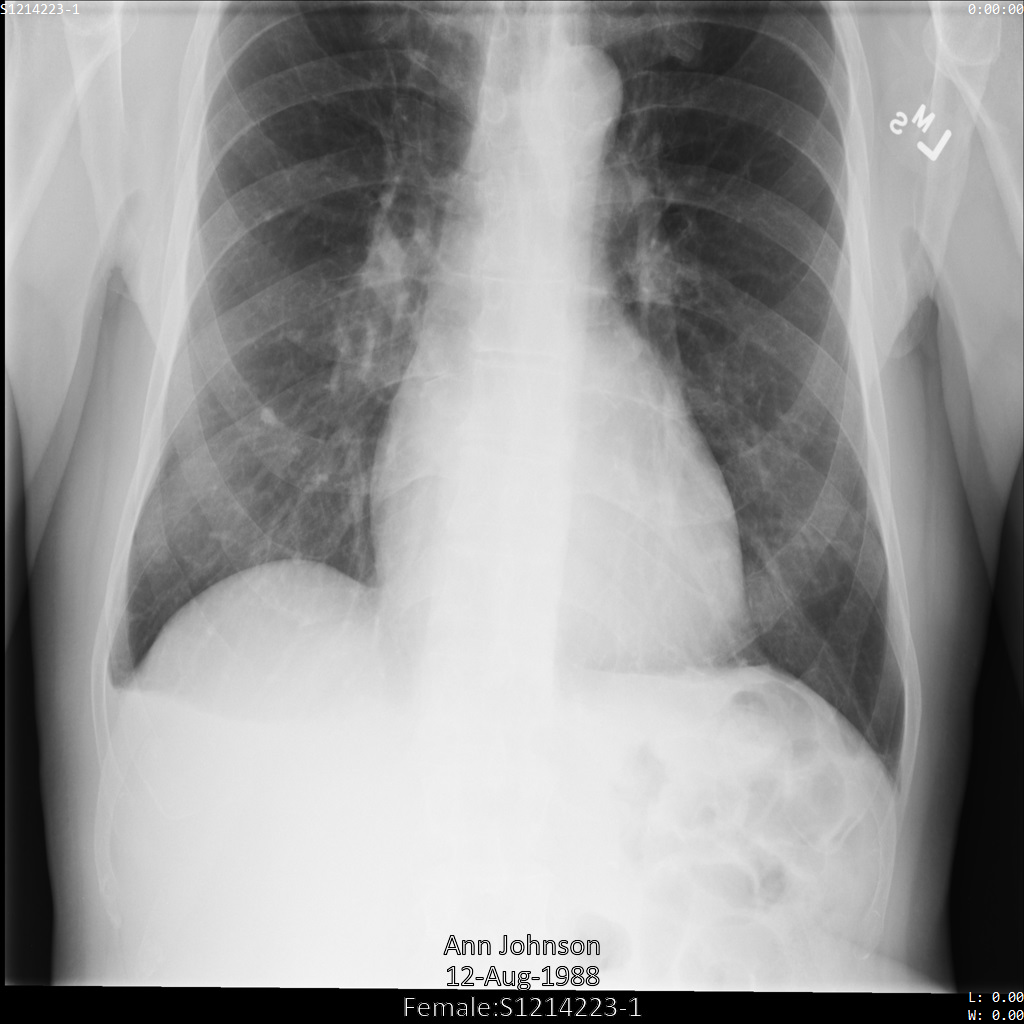

Después de enviar la imagen a la API de Cloud Healthcare, la imagen aparece de la siguiente manera. Mientras se ocultan los metadatos que se muestran en las esquinas superiores de la imagen, la información de salud protegida (PHI) quemado en la parte inferior de la imagen permanece. Para quitar también el texto quemado, consulta Oculta el texto quemado de las imágenes.